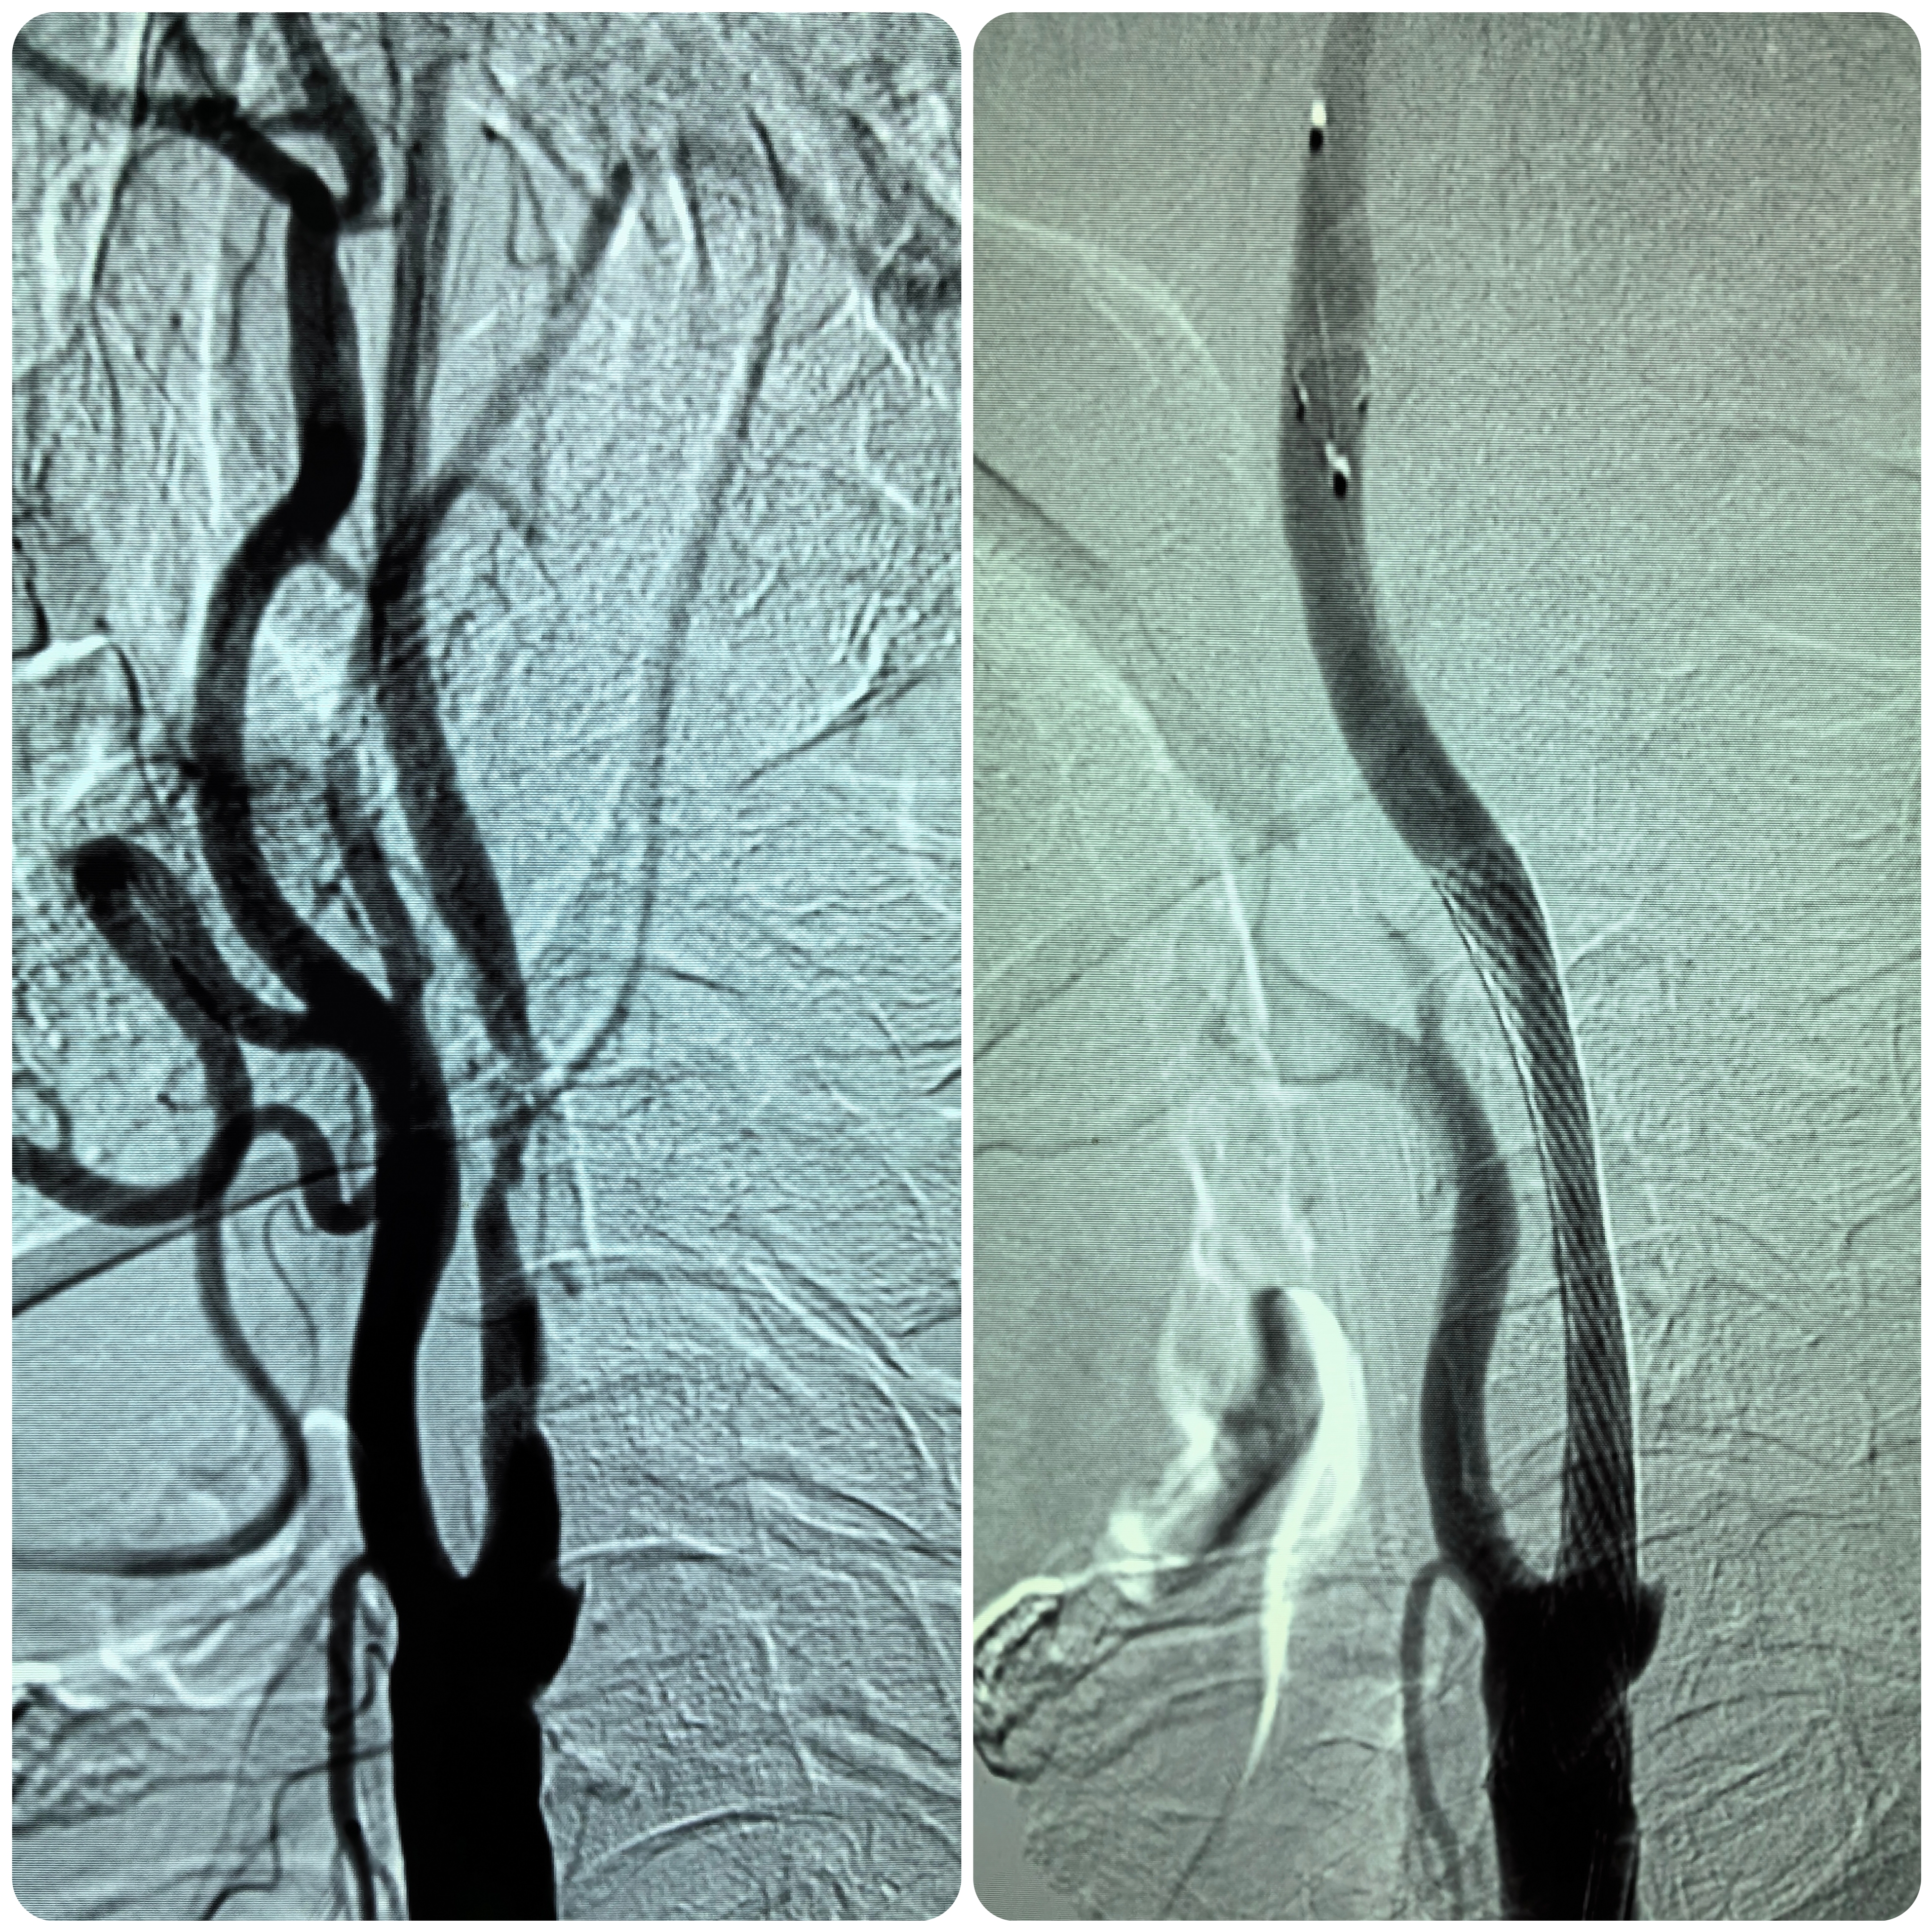

患者男性,70岁,体检发现双侧颈内动脉重度狭窄,1月前行右侧颈内动脉支架成形术,现为治疗左侧颈内动脉狭窄入院。既往高血压病史30年,口服硝苯地平控释片降压,血压控制130/80mmHg。

1、本例患者老年男性,双侧颈内动脉重度狭窄,治疗采取分期处理,间隔4周。

2、左侧颈内动脉从CTA看狭窄合并软斑,具备介入治疗指征。